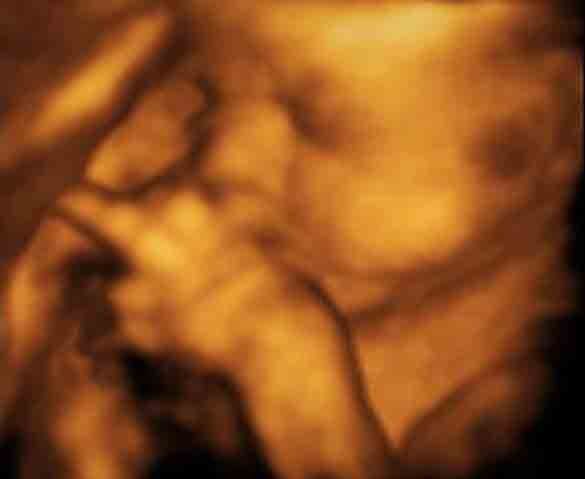

Có vẻ như mút ngón tay là trò chơi yêu thích của thai nhi bé bỏng này.